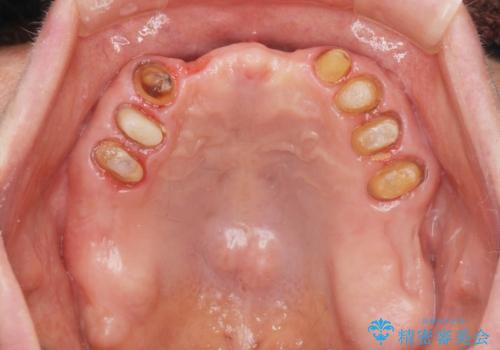

咬合の崩壊 金属床義歯で咬合機能の回復

- 「体調が悪く歯医者に行けない間にどんどん歯が悪くなってしまった、治療をしたい。」と咬合機能の回復を希望され来院されました。

「大規模な手術は避けたい。」と言う希望を鑑み、インプラントではなく残せる歯の連結セラミッククラウンの作製、金属床義歯を用いてしっかりと咬合機能を回復できるよう治療を進めます。